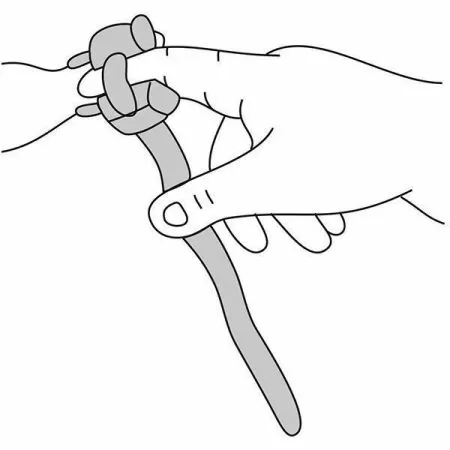

Датчик детский (манжета) |

1 |

Датчик пульсоксиметрический пальцевой |

1 |